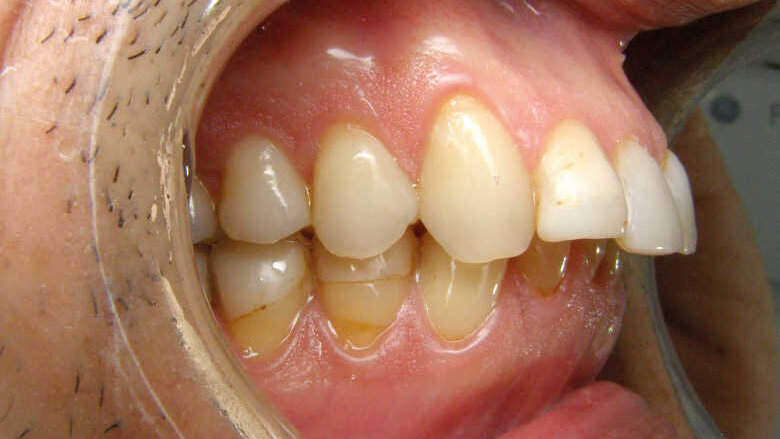

D’un point de vue dentaire le patient présente une Classe II division 1, avec une classe II molaire complète et une classe II canine.

- Présence d’un overjet et d’une supraclusion résiduelle.

- L’arcade supérieure est régulière mais les incisives sont en vestibulo version importante.

- L’arcade inférieure présente un encombrement dans le secteur antérieur associé à une version vestibulaire.

- Les milieux correspondent.